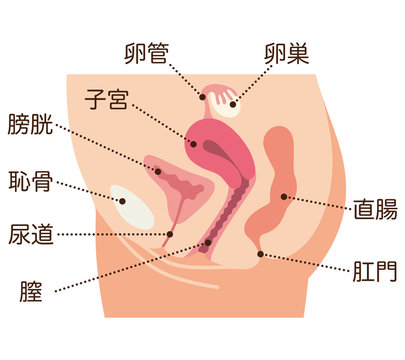

女性器の断面図 Listen さくやの囁き

子宮横からの断面図 名称付き メディカルイラスト図鑑 無料の医療 美容素材集

子宮 断面図 女性のからだのイラスト素材

骨盤 女性 解剖学 切断断面 卵巣 卵管 子宮 膀胱 膀胱 尿路 クリトリス 尿道 尿道括約筋 膣 外陰結腸 直腸括約筋が示される のイラスト素材